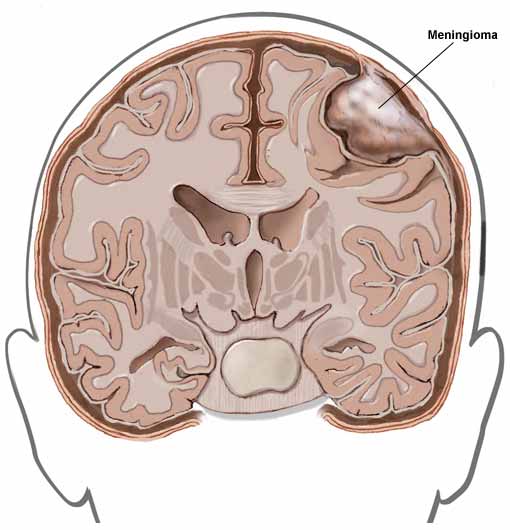

Meningiomas make up about one-fifth of all primary intracranial tumors. Meningiomas are usually slow growing. Approximately a quarter of patients with meningioma present with epilepsy. In the remainder the effects of the pressure of the growing tumor (headache, vomiting, etc.) often become evident first.

Simply, meningiomas are tumors that arise from the leptomeninges (tissue that serves as the lining of the brain). They develop from cells of arachnoid granulations, and they can occur throughout the supratentorial and infratentorial compartment. They are generally benign tumors, and only rarely do they undergo malignant transformation.